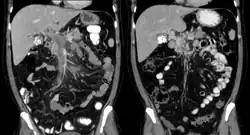

| Portal vein thrombosis seen with computed tomography. | |

The diagnosis of portal vein thrombosis is usually made with imaging confirming a clot in the portal vein; ultrasound is the least invasive method and the addition of the Doppler technique shows a filling defect in blood flow. PVT may be classified as either occlusive or nonocclusive based on evidence of blood flow around the clot.[5] An alternative characterization based on site can be made: Type 1 is limited to the main portal vein, Type 2 involves only a portal vein branch (2a, or 2b if both branches are affected), and Type 3 if clot is found throughout both areas.[8] Determination of condition severity may be derived via computed tomography (CT) with contrast, magnetic resonance imaging (MRI), or MR angiography (MRA). Those with chronic PVT may undergo upper endoscopy (esophagogastroduodenoscopy, EGD) to evaluate the presence of concurrent dilated veins (varices) in the stomach or esophagus.[3] Other than perhaps slightly elevated transaminases, laboratory tests to evaluate liver function are typically normal.[1] D-dimer levels in the blood may be elevated as a result of fibrin breakdown.